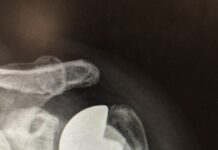

Endoprotezy stawu ramiennego: standard w Europie, w Polsce wciąż rzadkość

Protezoplastyka stawu biodrowego czy kolanowego to już standardowe operacje w Polsce – poddaje im się 70-80 tys. osób rocznie. Tymczasem wszczepienie protezy stawu ramiennego,...